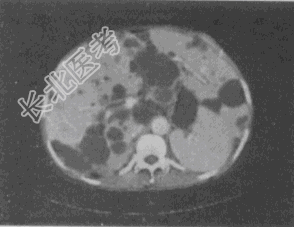

- 单项选择题男,56岁, 腹部包块伴高血压,CT扫描如图所示, 下列说法错误的是

A、双肾体积明显增大

B、双肾内可见多个大小不等的囊性病灶,呈蜂窝状改变

C、肝内可见多个大小不等的囊性病灶

D、考虑为多囊肾、多囊肝

E、考虑为双肾多发单纯性囊肿